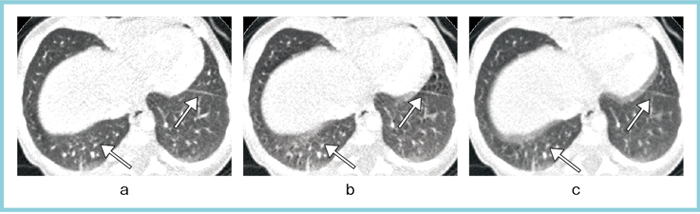

ハーフ再構成の際には,使用するデータを正しく選択することが必要である。われわれの施設では,模擬心電波形が出せる装置などを利用して,心電波形を入力しながら撮影を行い,再構成の際に波形情報を参照して,最適な時相のデータを抽出できるように調節する工夫をしている。図4は,aが最良の部分を選択したハーフ再構成,bが運任せの中央リコン,cがフルリコンだが,aでは肺も心臓もブレのないフェーズが選択できている。これによって,小児の血管系の3D画像なども精度の高い血管像の再構成が可能で,先天性心奇形や大血管奇形の診断に有用である。

図4 心電波形を参照したハーフ画像再構成

a:ハーフリコン(最適),b:ハーフリコン(中央),c:フルリコン